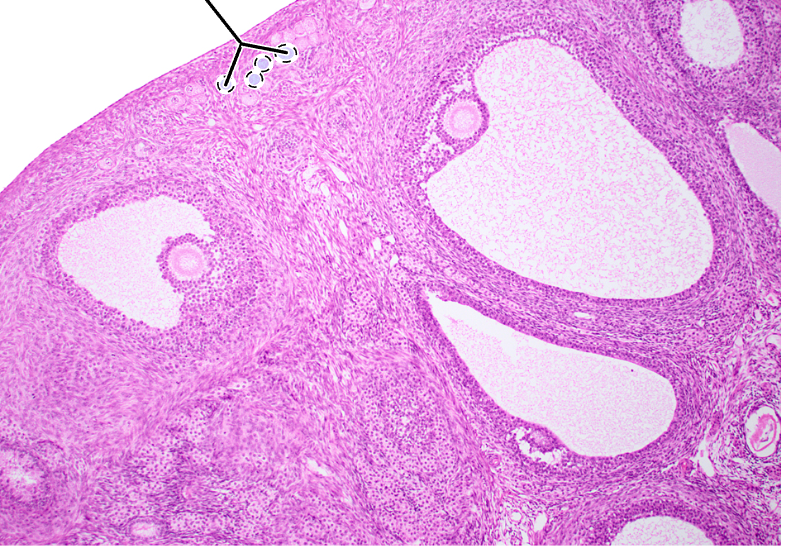

ovary (mature tertiary follicles)

oocyte

zona pellucida

corona radiata

antrum